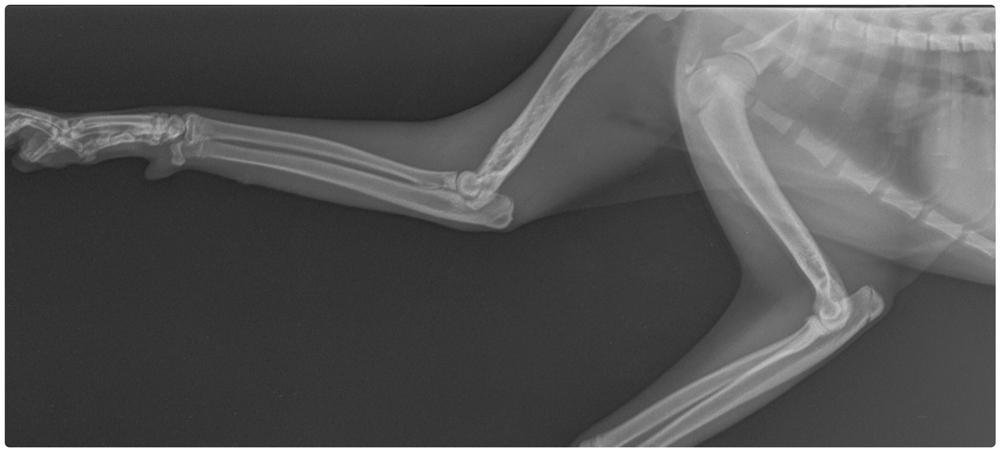

Рентген или компьютерная томография (КТ). Первое исследование проводят только после 2 лет. До этого возраста снимок неинформативен, поэтому вместо него делают объемную проекцию пораженной конечности с помощью КТ.